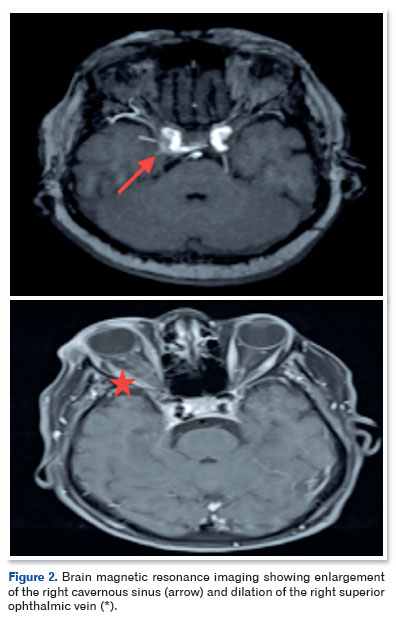

Cranial magnetic resonance imaging (Figure 2) and MRA (Figure 3) showed sinuous and ectatic vascular structures adjacent to the posteromedial wall of the intracavernous segment of the right ICA, as well as asymmetric dilation of the ipsilateral superior ophthalmic vein and grade II proptosis. These findings were consistent with the diagnosis of a direct CCF.

Clinically, direct CCFs cause an abrupt rise in orbital venous pressure, resulting in proptosis, chemosis, conjunctival congestion, pulsatile bruits, and paralysis of the III, IV, and VI cranial nerves. Dandy’s triad (proptosis, orbital bruit, and conjunctival congestion) is highly suggestive4. Digital cerebral angiography is the gold-standard diagnostic examination; however, other imaging tests, such as magnetic resonance angiography (MRA), may demonstrate dilation of the superior ophthalmic vein and alterations in the cavernous sinus5.